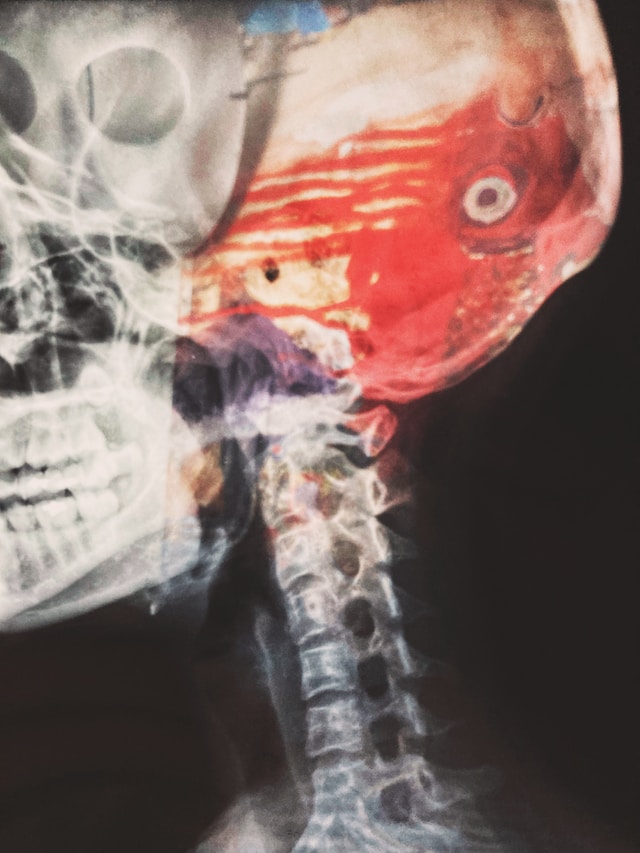

Recent scientific discoveries have revealed a remarkable and intricate connection between our gut and brain health. The gut microbiome, a vast ecosystem of microorganisms residing in our digestive tract, has emerged as a critical player in regulating our mental well-being. In this article, we delve into the fascinating world of the brain-gut connection, shedding light on how our gut microbiome influences brain health.

The gut microbiome consists of trillions of microorganisms, including bacteria, viruses, and fungi, which coexist in symbiosis with our bodies. These microbes play essential roles in digestion, nutrient absorption, immune system regulation, and even the production of certain neurotransmitters.

One of the most intriguing aspects of the gut microbiome is its ability to communicate with the brain through the gut-brain axis, a bidirectional signaling pathway. This communication occurs via various channels, including the vagus nerve, immune system molecules, and metabolites produced by gut microbes.